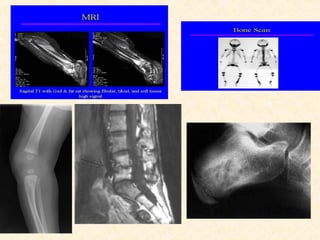

 X-ray –

 Radionuclide bone scans

 Computed tomography scan (Also called CT or CAT

 Magnetic resonance imaging (MRI

HOW IS OSTEOMYELITIS DIAGNOSED Blood tests  Complete blood count (CBC)  Erythrocyte sedimentation rate (ESR)  Reactive protein (CRP)  Needle aspiration or bone biopsy  X-ray –  Radionuclide bone scans  Computed tomography scan (Also called CT or CAT scan.)  Magnetic resonance imaging (MRI  Ultrasound -